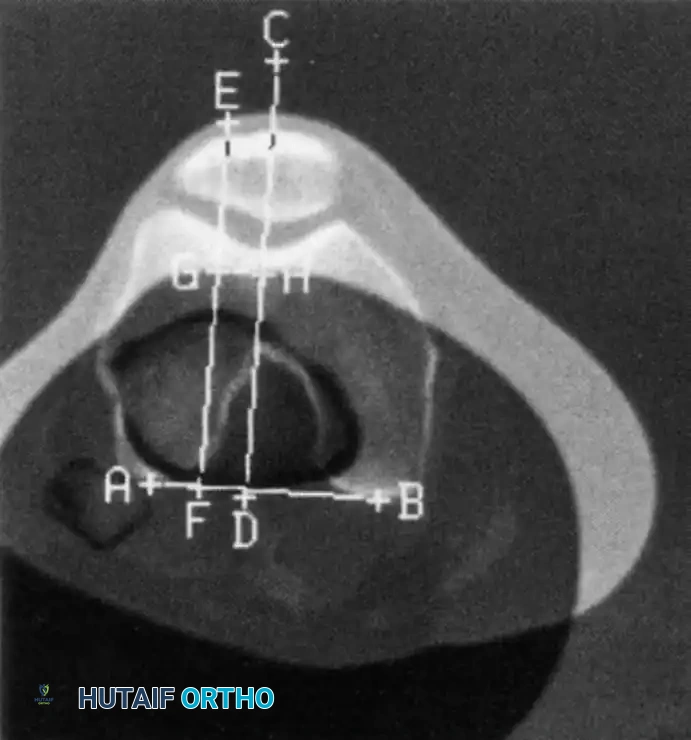

While plain radiographs provide excellent baseline data, Computed Tomography (CT) is the definitive modality for quantifying the lateralization of the tibial tubercle relative to the femoral trochlea—a critical metric known as the Tibial Tubercle-Trochlear Groove (TT-TG) distance.

FIGURE 47-11: Lines used to calculate tibial tubercle lateralization using CT. A line is drawn on a superimposed image between the posterior margins of the femoral condyles (AB). Two lines are drawn perpendicular to this: one bisecting the femoral trochlear groove (CD) and one bisecting the anterior tibial tuberosity through a chosen point in the center of the patellar tendon insertion (EF). The distance between these two lines (GH) is measured in millimeters.

A normal TT-TG distance is typically less than 15 mm. A measurement approaching or exceeding 20 mm is considered highly abnormal and represents a significant biomechanical vector pulling the patella laterally. In the setting of recurrent instability, a TT-TG > 20 mm is a strong indication for a bony realignment procedure, such as a Fulkerson anteromedialization osteotomy.